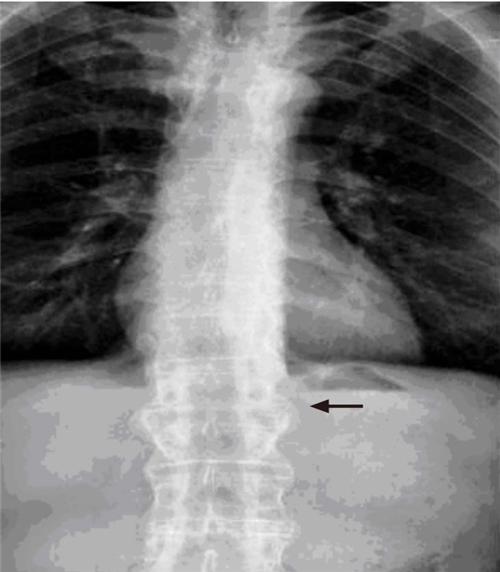

相关图片